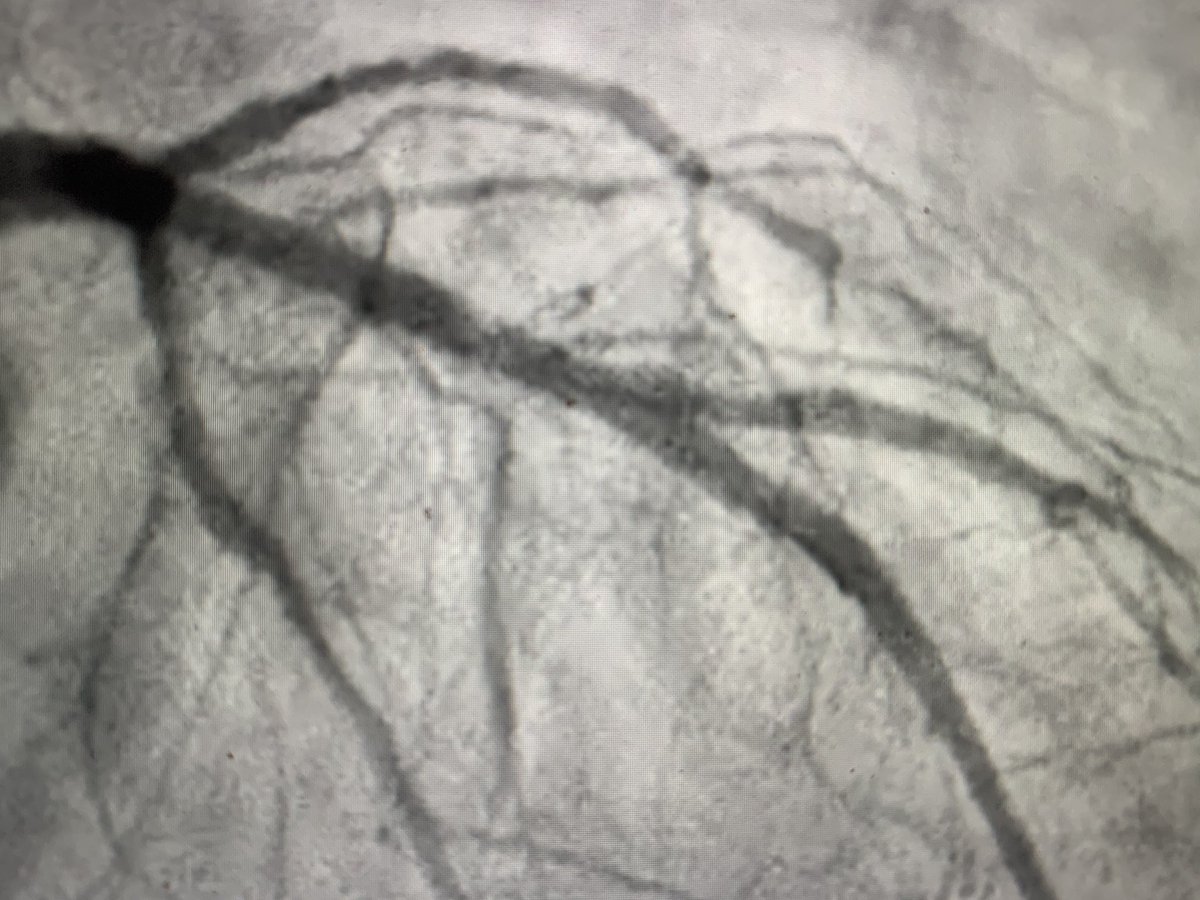

69 yo M surg

s/p Impella supp, IVUS DK Crush of pLAD / D1 six months ago p/w NSTEMI.

2 wires, PCI LAD, post PCI - ostial D1 looks worse.

Re-wired with Fielder, 1.0 Sapphire,

, Wolverine.

Do you re-stent D1? If so, technique and wire you

b/w stents?

#radialfirst pic.twitter.com/rtHrUrBnUz